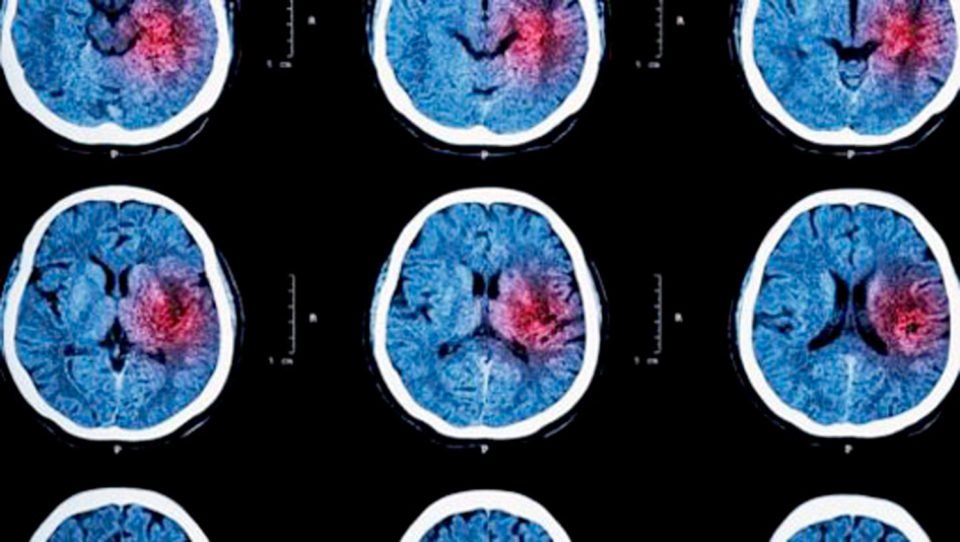

La première cause de handicap acquis de l’adulte

Parfois nommé « attaque cérébrale », l’accident vasculaire cérébral (AVC) correspond soit à l’obstruction, soit à la rupture d’un vaisseau sanguin dans le cerveau. Il peut survenir à tout âge chez l’adulte. En raison du risque de dommages irréversibles sur le cerveau, il s’agit d’une urgence médicale absolue qui nécessite d’appeler le 15 (Samu) ou le numéro d’urgence européen (112) pour une prise en charge immédiate. L’arrivée récente de la thrombectomie (mécanique), en plus de la thrombolyse (pharmacologique), a considérablement amélioré la prise en charge des patients.